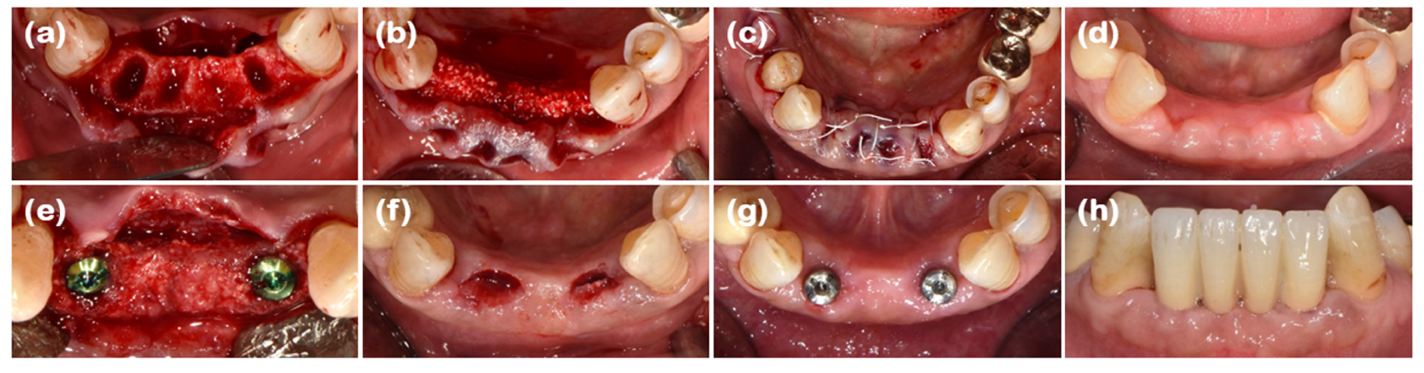

2.3. Case 3 (Multiple Anterior Teeth, Periodontitis, and Labio-Lingual Collapsed Extraction Region)